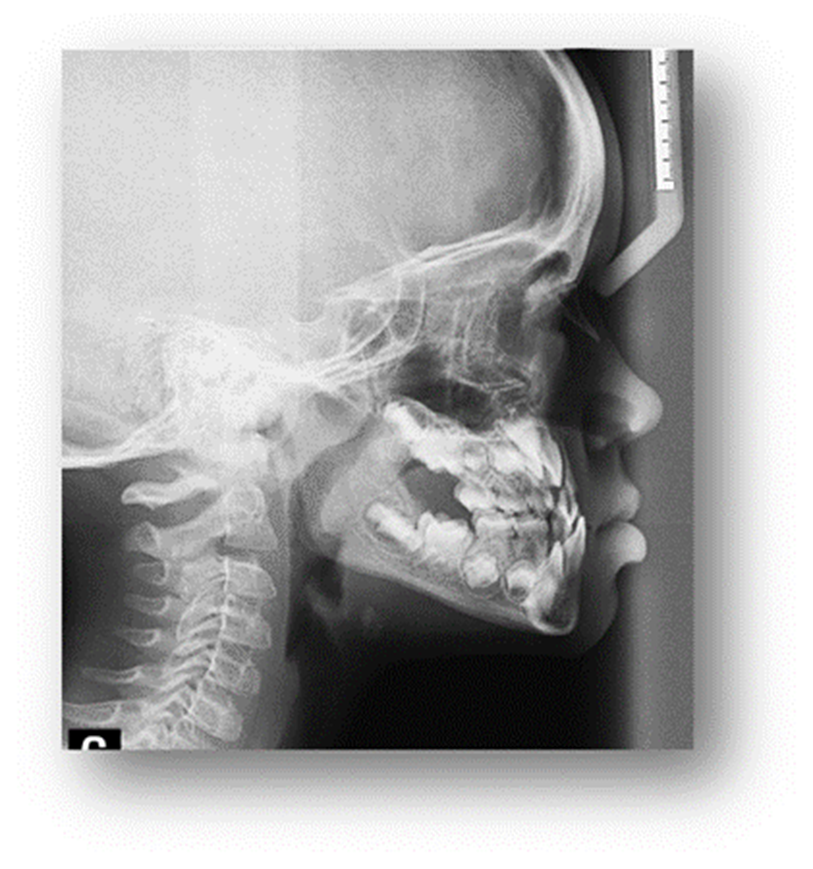

Autor: María Gabriela Flores Bracho. Fuente: Historia Clínica de M. C. M. H. 6 años. 04- 2010

Figura 6. Radiografía de perfil o lateral.